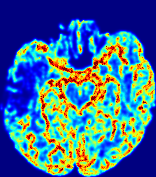

Slice #1Slice #2Slice #3Slice #4Slice #5Slice #6Dgtsuperscript𝐷gtD^{\text{gt}}Refer to captionRefer to captionRefer to captionRefer to captionRefer to captionRefer to caption(a)Refer to captionRefer to captionRefer to captionRefer to captionRefer to captionRefer to caption(b)Refer to captionRefer to captionRefer to captionRefer to captionRefer to captionRefer to caption(c)Refer to captionRefer to captionRefer to captionRefer to captionRefer to captionRefer to caption(d)Refer to captionRefer to captionRefer to captionRefer to captionRefer to captionRefer to caption(e)Refer to captionRefer to captionRefer to captionRefer to captionRefer to captionRefer to caption(f)Refer to captionRefer to captionRefer to captionRefer to captionRefer to captionRefer to captionRefer to caption000.060.060.060.120.120.120.180.180.180.240.240.240.300.300.30(mm2/s)𝑚superscript𝑚2𝑠(mm^{2}/s)

Figure 13: PIANO effectiveness and robustness testing: diffusion imaging via diffusion. Top row shows Dgtsuperscript𝐷gtD^{\text{gt}} used for simulating the ground truth pure diffusion. (a)-(f) refer to the results for D𝐷D estimated from the ground truth pure diffusion image time-series where Rician noise at levels 0%, 2%, 4%, 6%, 8%, 10% was added respectively.

Similarly, starting from the same initial condition C0superscript𝐶0C^{0} as in the ‘Advection Imaging’ experiment for each patient, we simulate concentration time-series {Cti(Ω)|i=0, 1,, 40}conditional-setsuperscript𝐶subscript𝑡𝑖Ω𝑖0140\{C^{t_{i}}\in\mathbb{R}(\Omega)|i=0,\,1,\,\ldots,\,40\} via a diffusion PDE, where we define the ground truth diffusivity D:=Dgtassign𝐷superscript𝐷gtD:=D^{\text{gt}} via the ADC map of the ISLES 2017 training set (ADC values are scaled by 0.000010.000010.00001 to ensure numerical stability):

Note this is likely not a spatially representative ground-truth for perfusion imaging, as it measures different effects from diffusion imaging. However, we still use it as a quasi-realistic pattern of diffusivity in the brain. We also added 2%, 4%, 6%, 8%, 10% levels of Rician noise to obtain simulations of ‘Diffusion Imaging’. The estimated Destsuperscript𝐷estD^{\text{est}} given concentrations of all noise levels for one patient are shown in Fig. 13, PIANO estimation results for all patients are summarized in Fig. 11 (b). Again, PIANO demonstrates its capability to recover the underlying diffusion field. In Fig. 13, when the noise level is increasing, some noisy patterns indeed appear in the associated Destsuperscript𝐷estD^{\text{est}}. Note that the ground truth diffusivity applied in this simulation experiment is about ten times larger than the diffusivity estimated in reality (Fig. 3, Fig. 4).